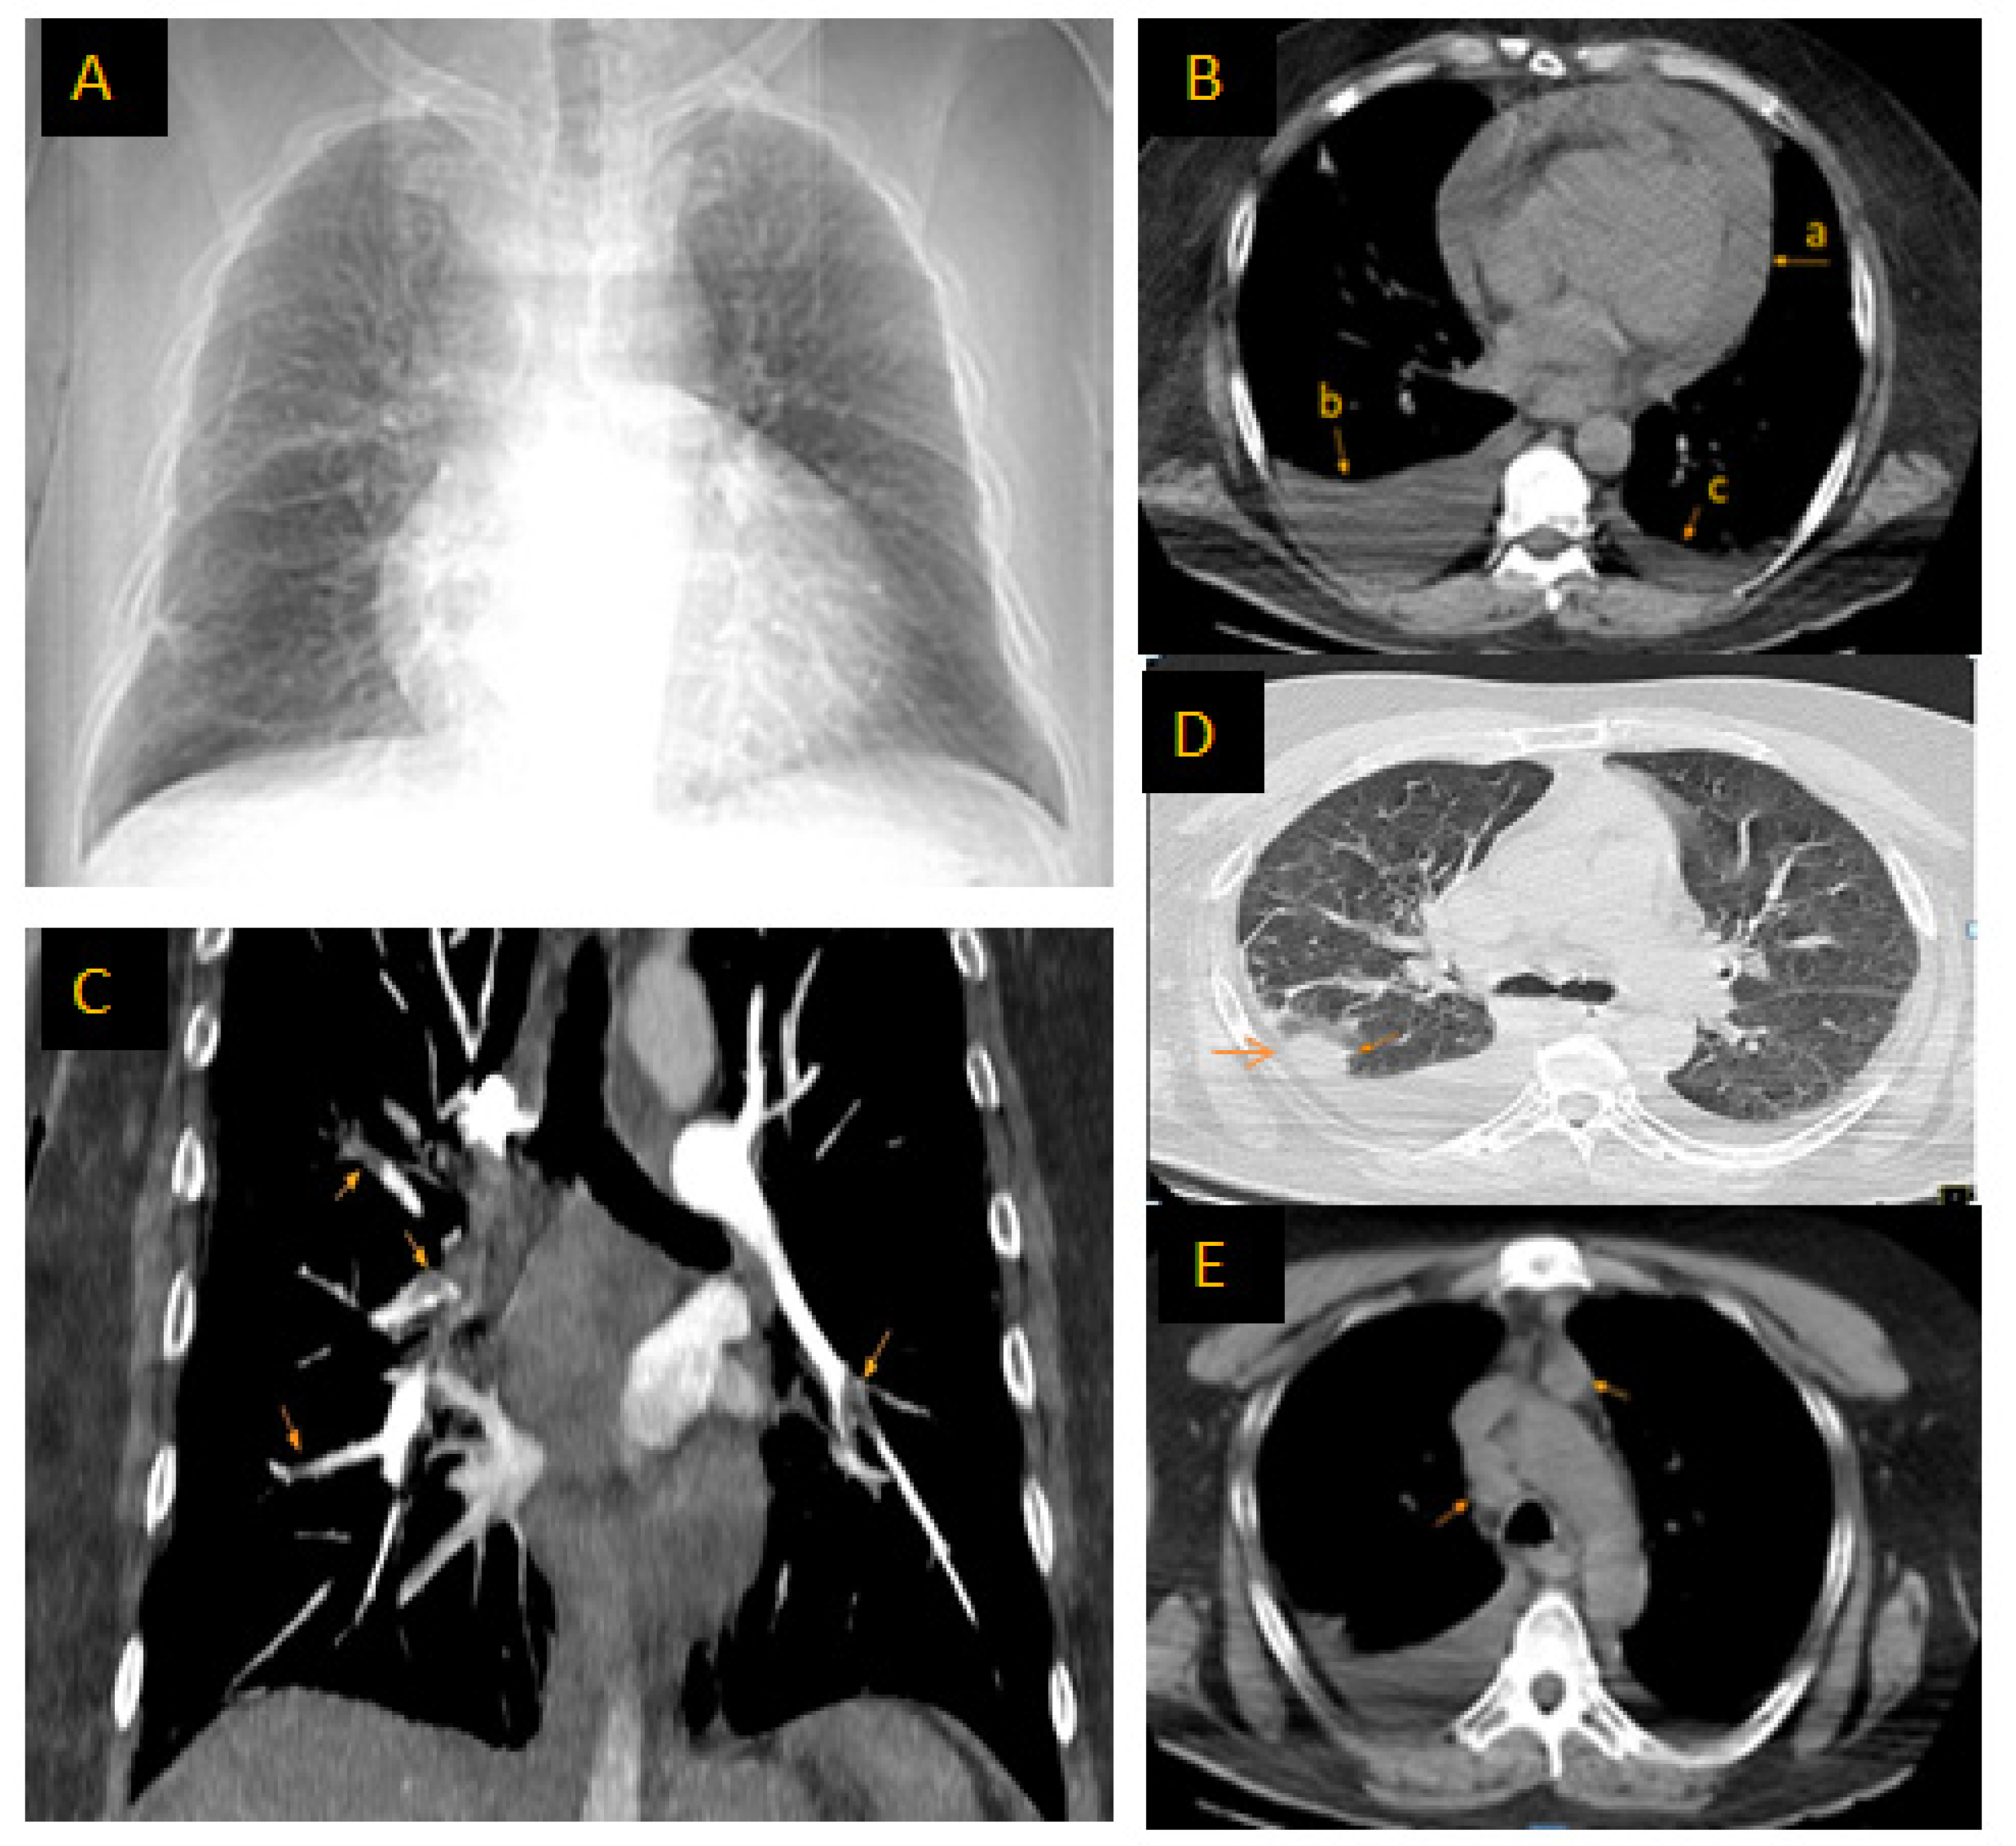

| El Rahalete et al./2023 [30] | 1/F/38 years | Moderately differentiated adenocarcinoma of the lung | Parenchymal lymph node of the upper lung lobe | Hepatic metastasis | Deep vein thrombosis of the left lower limb, pericardial tamponade, bilateral PE, bilateral pulmonary effusion | Respiratory distress, chest pain | Twin pregnancy |